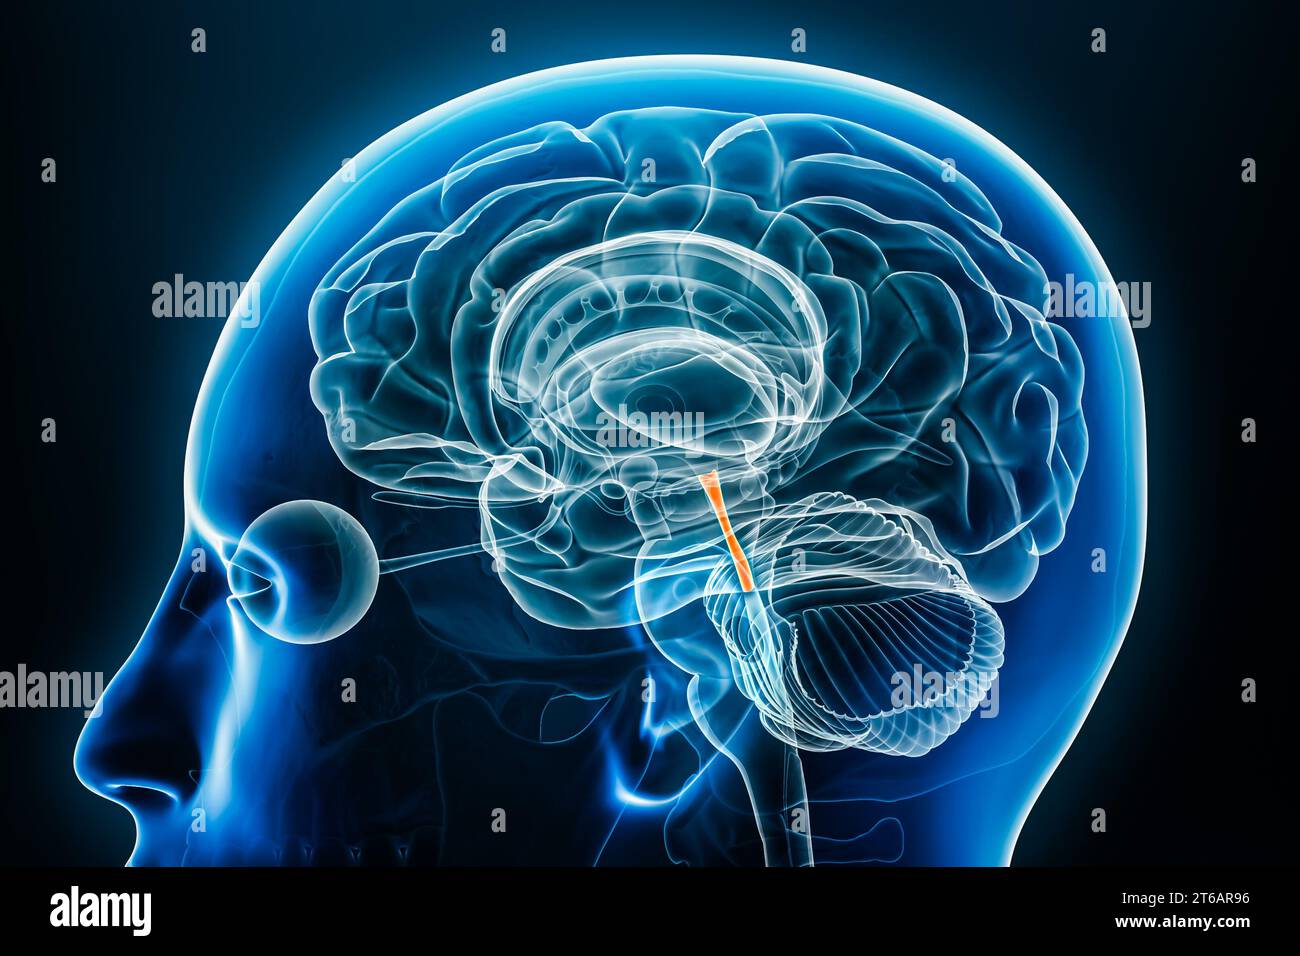

RF2T030FH–Röntgenprofilansicht des Sylvius oder des zentralen Aquädukts des Gehirns 3D-Rendering-Illustration. Menschliche Körperanatomie, Medizin, Biologie, Wissenschaft, Neurowissenschaft,

RF2T6AR8J–3D-Rendering-Illustration für die Röntgenansicht des Gehirns oder des Sylvius aquädukt. Anatomie des menschlichen Gehirns und des Ventrikelsystems, Medizin, Gesundheitswesen, Biologie, Wissenschaft,

RF2T6AR96–Röntgenprofil des Gehirns oder sylvius aquädukt Nahansicht 3D-Rendering-Illustration mit Körperkonturen. Anatomie des menschlichen Gehirns und des Ventrikelsystems, med